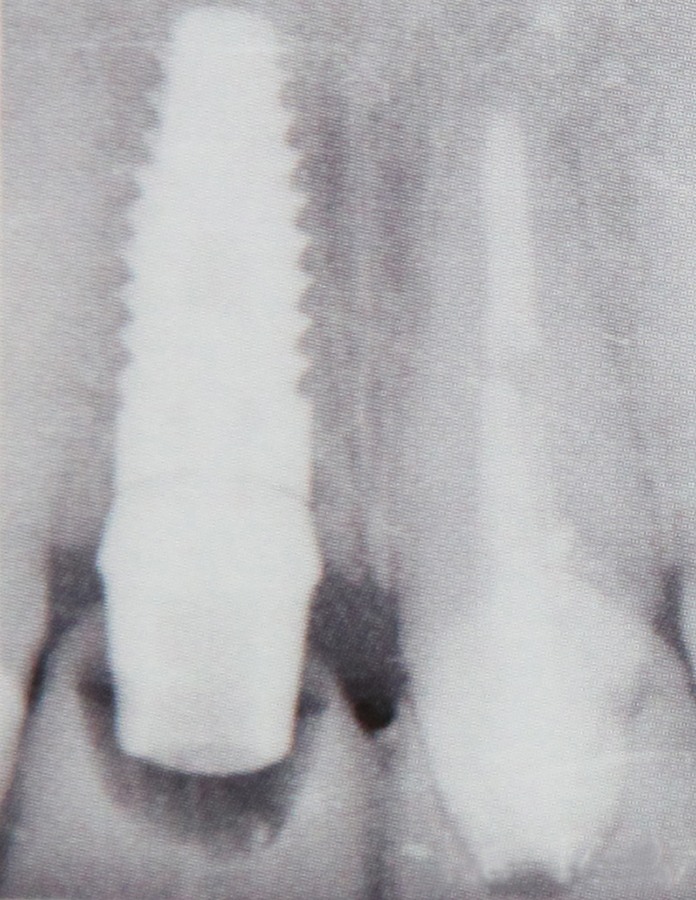

Implantele dentare reprezinta la ora actuala singura posibilitate de a inlocui dintii lipsa prin protezare fixa rezultand o dentitie foarte apropiata de dintii naturali. Implantele dentare sunt niste radacini artificiale realizate din titan care se insera in os. Dupa o perioada de aproximativ 6 luni perioada necesara pentru integrarea implantului, acestuia i se ataseaza un bont protetic pe care ulterior se fixeaza coronita de ceramica sau proteza.